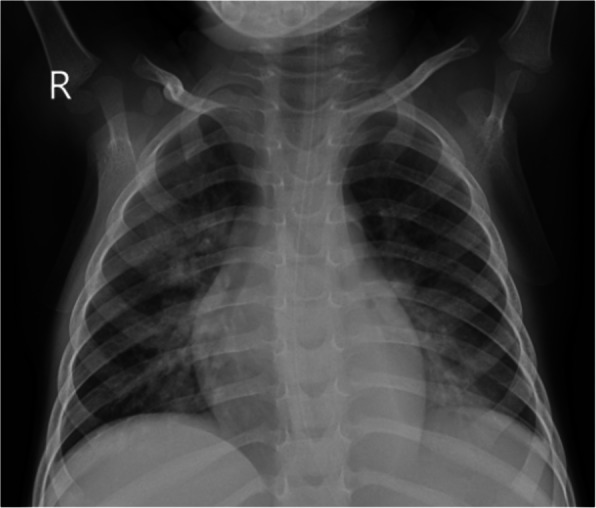

On the ninth day of admission he developed progressive respiratory distress and new foci of patchy consolidation on chest radiograph (Fig. 8), but remained afebrile.

Fig. 8.

Case 3, Chest radiograph on day 9 of admission. Chest radiograph showing bilateral confluent air space opacification in the bilateral perihilar region, with patchy consolidation in the right upper lobe and left lower lobe